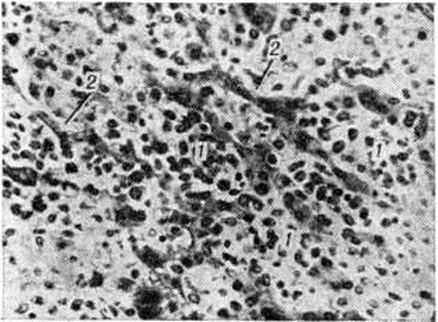

Лейкозная инфильтрация ткани селезёнки и лимфатических, узлов сопровождается уменьшением размеров (рисунок 2) и числа фолликулов вплоть до полного их исчезновения. В селезёнке часто наблюдается инфильтрация трабекул с разволокнением стенок трабекулярных сосудов, с деформацией и сужением их просвета, имеются поля кровоизлияний. В лимфатических, узлах вначале возникают очаговые инфильтраты, которые по мере прогрессирования болезни увеличиваются в размерах, и поражение становится диффузным.